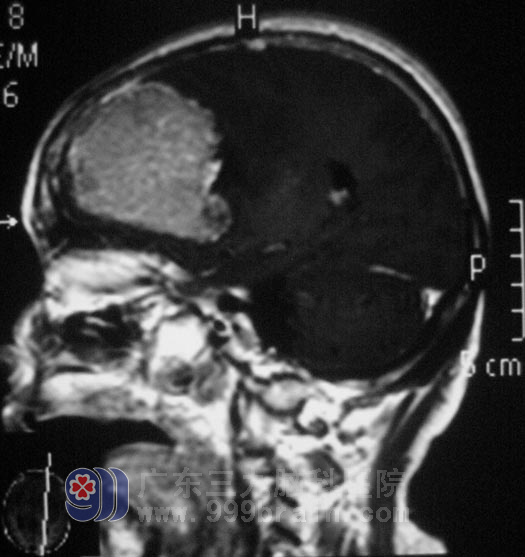

上面就是从马婆婆颅内切出的、折磨着她不能说话、不能走路、直径约6cm的肿瘤。http://www.999brain.com/

几经周折,他们来到广东三九脑科医院。入院时,马婆婆精神差,呈嗜睡状,右下肢I级,右上肢II-III级。综合神经外科 鲁明主任根据影像检查,考虑肿瘤有卒中的可能。9月5日,由鲁明主任主刀,在全麻下经改良翼点入路行左额部占位性病变切除术,术中见额部颅骨明显被肿瘤侵袭,脑组织张力较高,在显微镜下从病变周围沿硬膜逐步分离,整块切除病变组织,肿瘤大小6.3cm×5.0cm×5.4cm,手术过程顺利,术中出血约400ml。

术后第一天,马婆婆的语言功能、肢体活动功能基本恢复。拆完线后便能自行下床活动。儿女们都没有想到母亲手术后会出现这么满意的结果。术后病理结果为:(左额部)脑膜瘤,WHO I级。http://www.999brain.com/